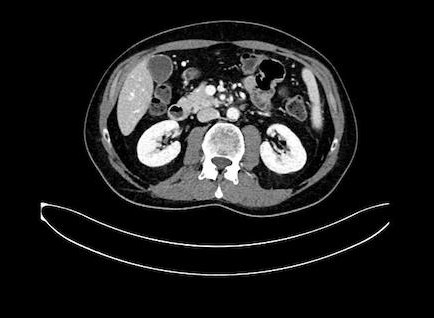

En dat is ook zo, want op deze foto is te zien waar hij ligt (lieten ze ons zien)

In het midden zit een mooie stip (ader) En daar schuin boven zie je nog wat lichts (ook ader). Daar tussen zit een grijze klodder… dat is ‘m. De witte delen zijn aders, en daar moet hij dus los van komen te liggen.